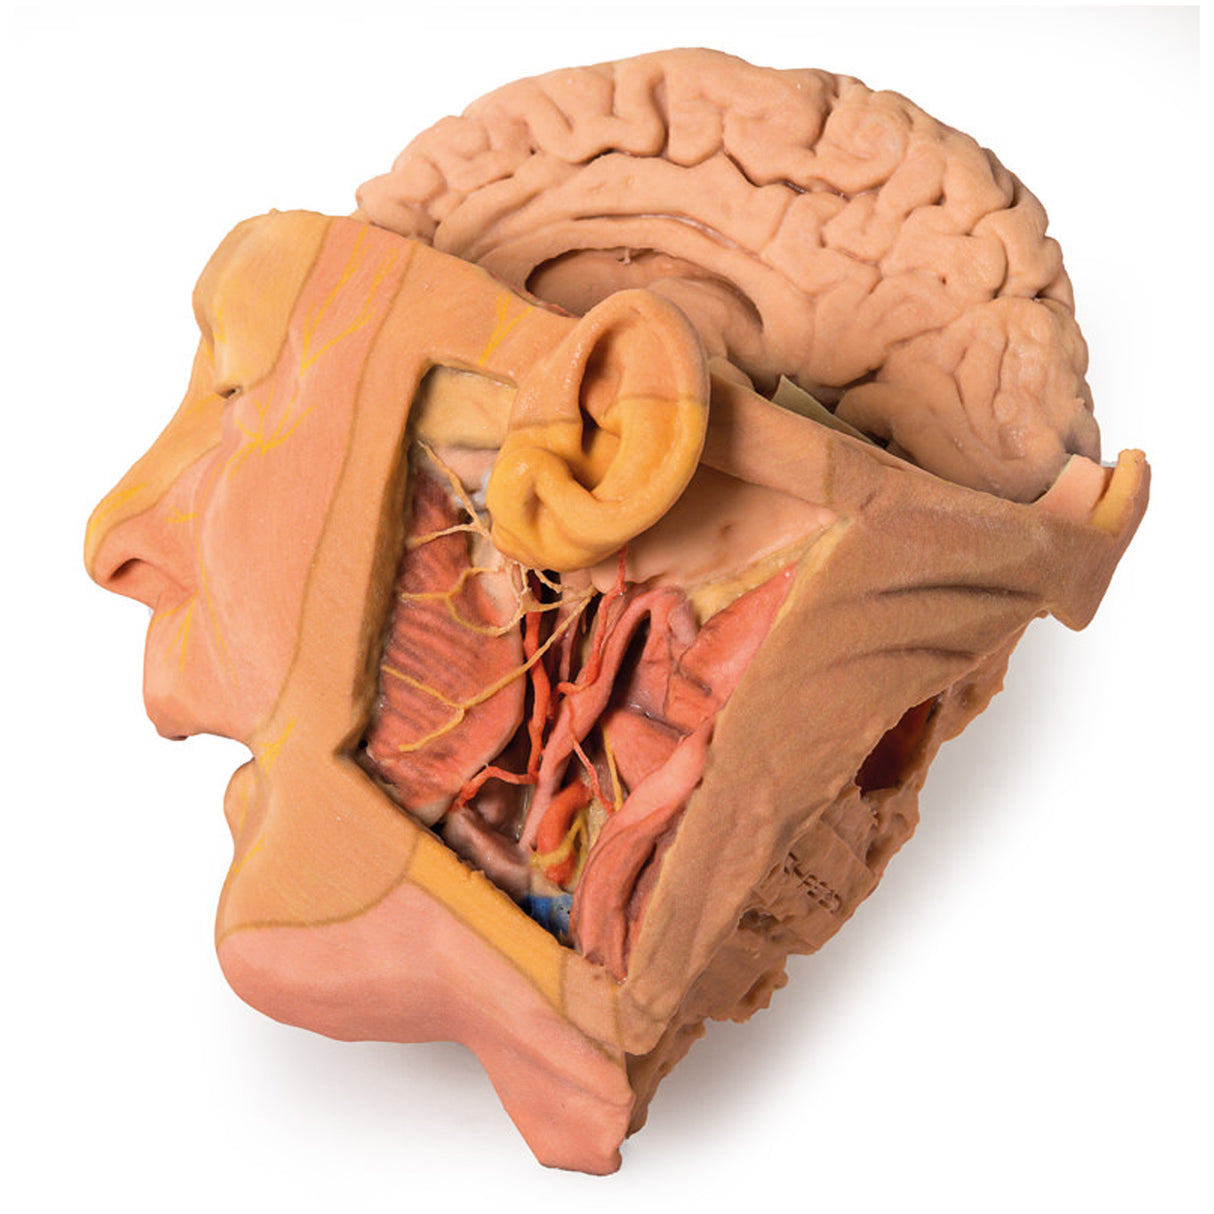

This 3D print provides a detailed view of head and neck anatomy, showing different structures depending on the perspective.

Lateral Face and Parotid Region

A window exposes the parotid region, with the pinna intact and the mastoid process revealed by reflecting the sternocleidomastoid (SCM). The parotid gland is removed to display hidden structures, including the posterior digastric, masseter muscle, and mandibular condyle in the TMJ. The external carotid artery (ECA) and its branches, internal jugular vein (IJV), hypoglossal, vagus, spinal accessory, and facial nerves are clearly visible. Facial dermatomes are illustrated via the trigeminal nerve branches.

Medial Surface and Key Vessels

The parasagittal section reveals the lateral ventricle, cerebral peduncle, posterior cerebral artery, and the tentorium cerebelli. The internal carotid artery in the cavernous sinus is shown lateral to the optic chiasm. Additional structures include the mouth, tongue, associated muscles, nasal cavity, nasopharynx, and cervical vertebrae.